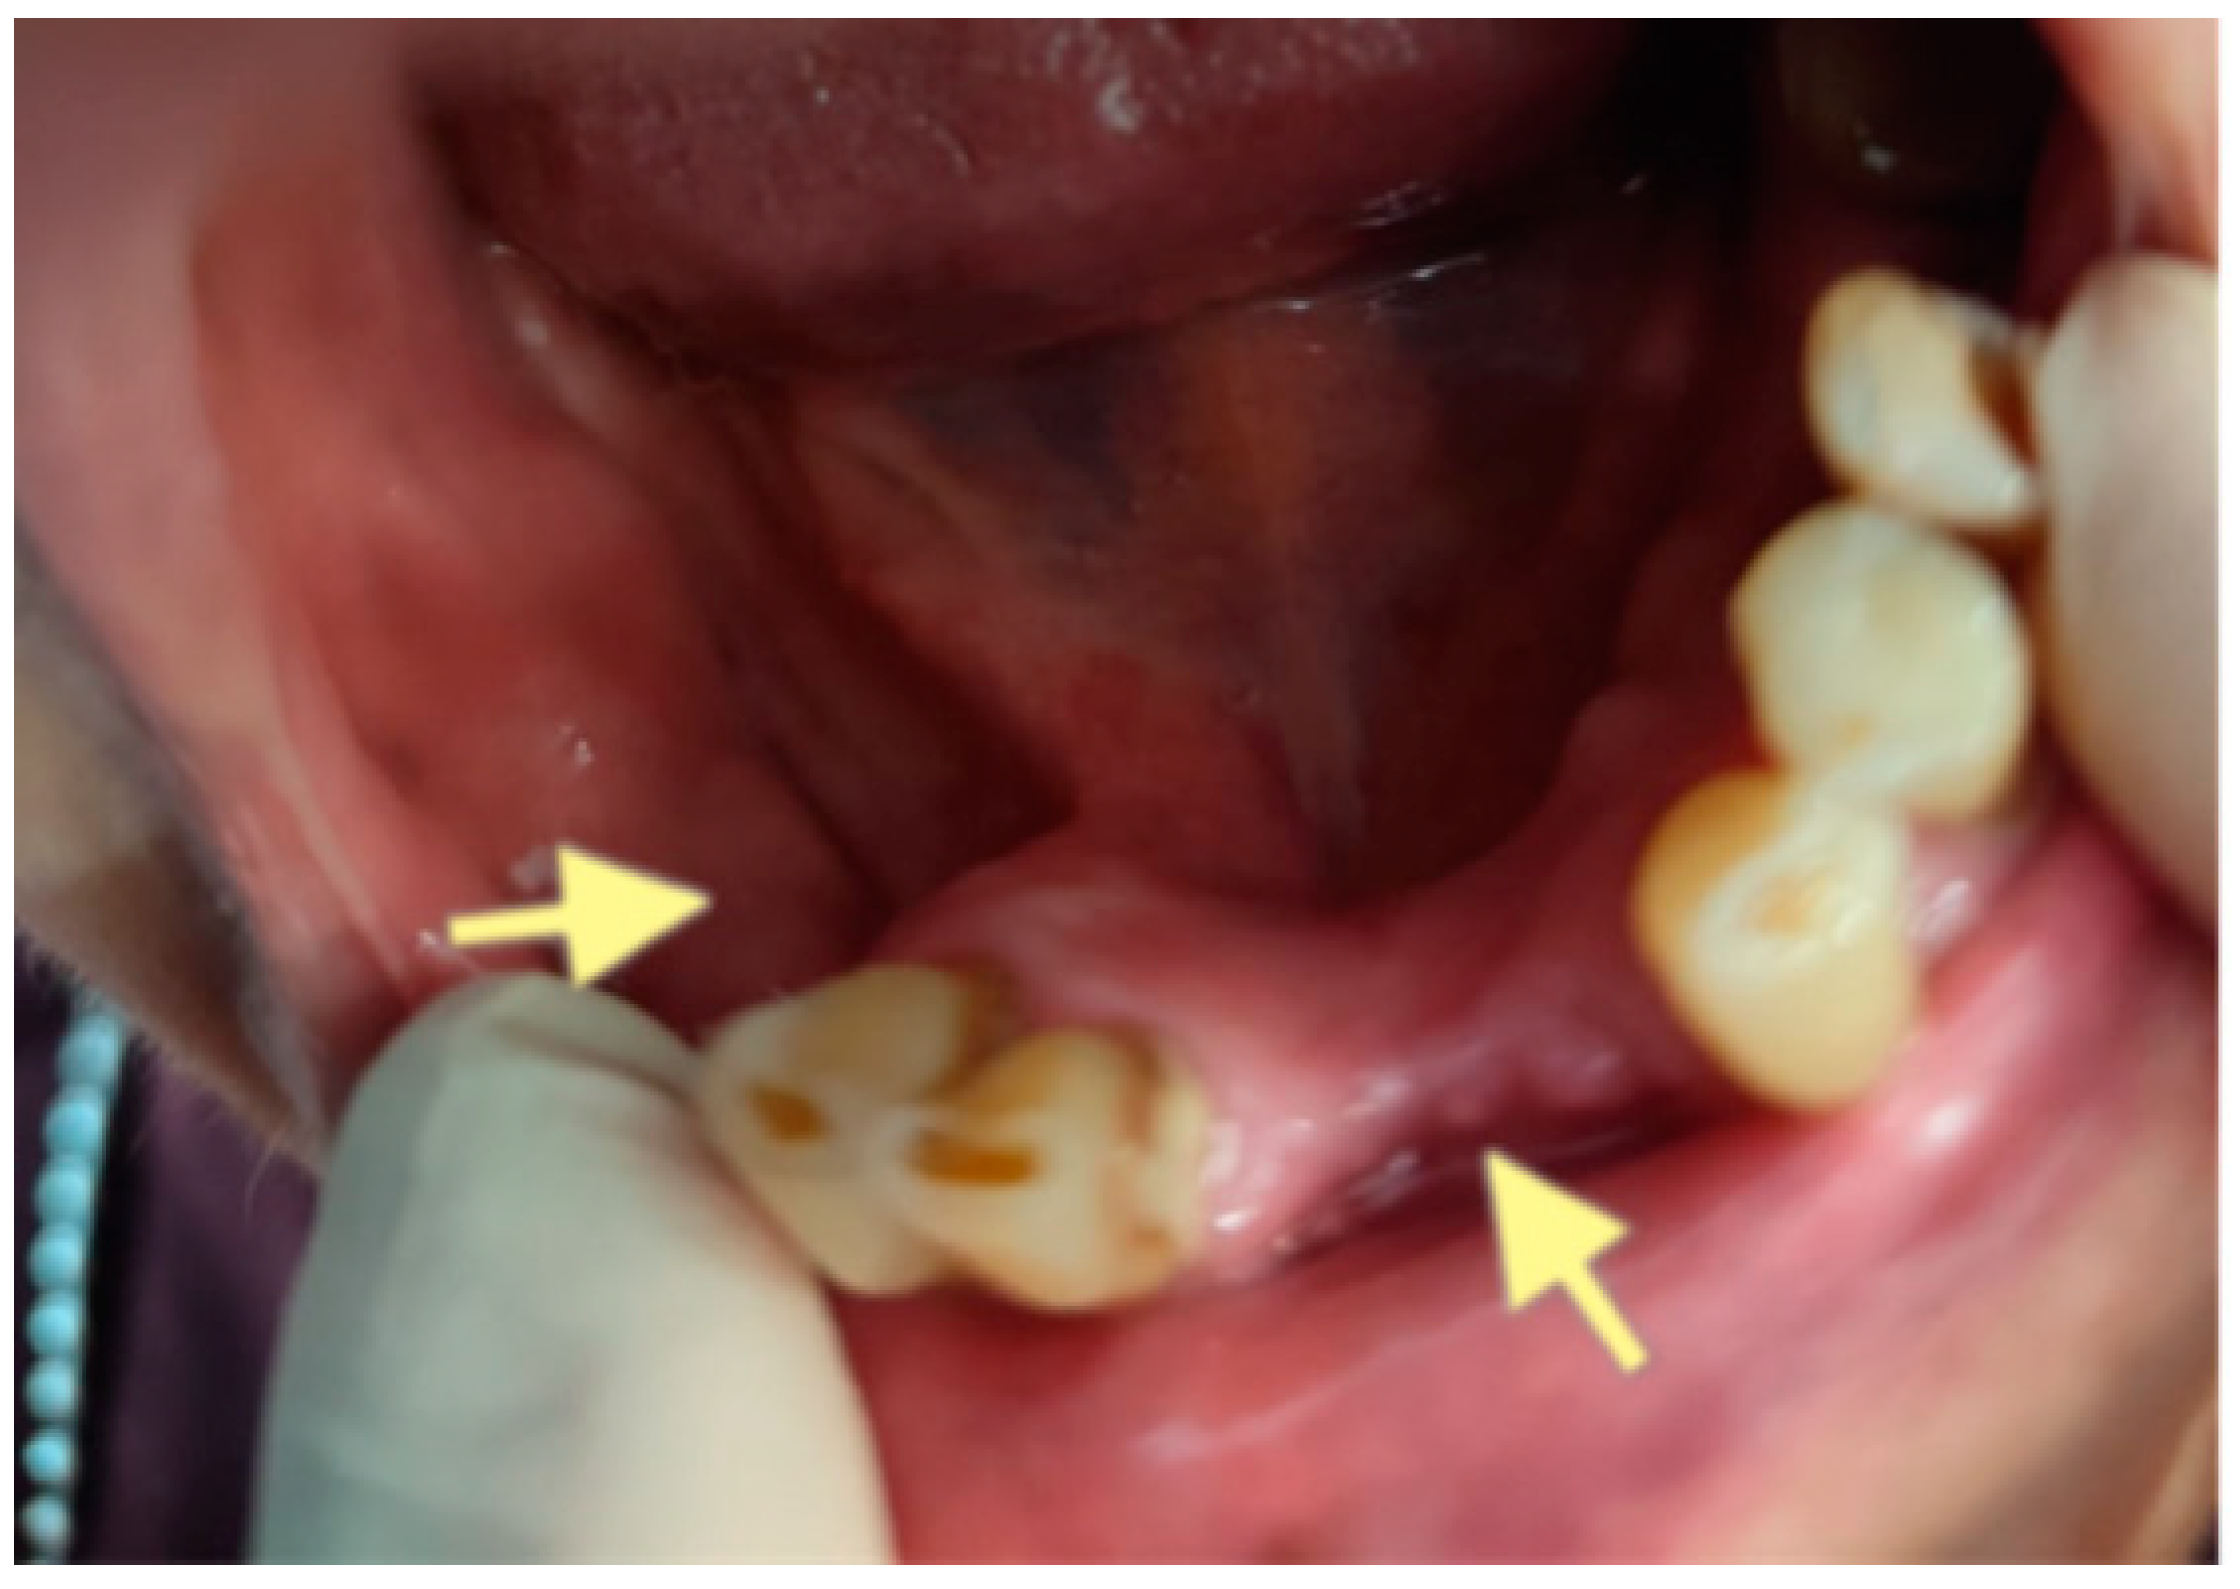

The third patient was a 75-year-old female with osteonecrosis of the mandible and maxilla in the fourth and in the second quadrant (see Figure 7, Figure 8 and Figure 9). The patient had third-stage jaw osteonecrosis. In 2023, the patient was diagnosed with osteonecrosis of the upper and lower jaw caused by antiresorptive therapy (until August 2021, the patient regularly used Zolendronic acid; then, this drug was replaced by the RANKL inhibitor Denosumab). The treatment was periodically complicated by submandibular and submental abscesses. In addition, due to the progression of the underlying disease, constant courses in chemotherapy were administered. The patient underwent three operations, which included sequestrectomy of the jaw with simultaneous use of A-PRF, antrotomy with revision of the maxillary sinus, closure of the oroantral communication, and opening and revision of abscesses of the soft tissues (see Figure 10 and Figure 11)

Figure 7.

CT of the head and facial bones (16 December 2024).